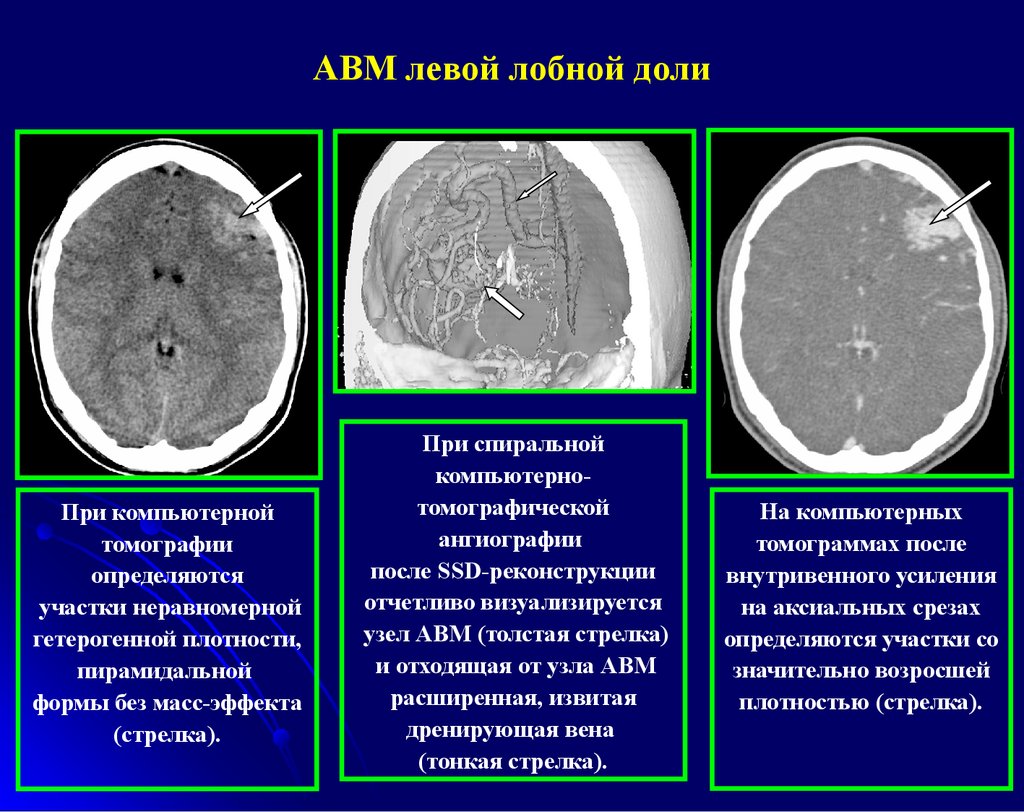

Мр картина венозной ангиомы левой гемисферы мозжечка - 96 фото